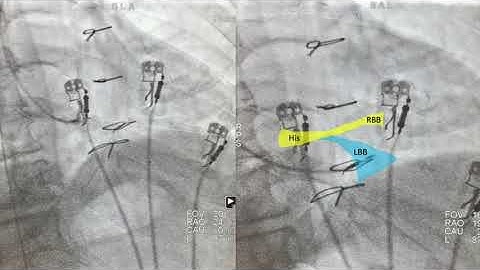

Left bundle branch pacing with stylet-driven lead